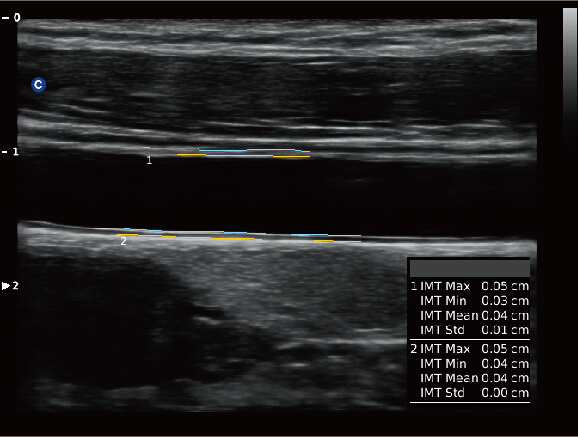

Función auto de la IMT

Automáticamente rastrea la intima y mide su espeso. Esto le permite medir la íntima más rápido y de forma más precisa.

.jpg)